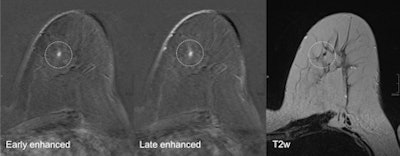

A 52-year-old patient who had breast cancer five years previously. MRI detected focus in the left craniomedial breast called BI-RADS 4, and a second opinion was requested. All images courtesy of Dr. Pascal Baltzer."Breast MRI is technically demanding, requiring excellent fat saturation, high spatial resolution, and rapid performance of postcontrast sequences," she said. "Common causes of false-positive diagnoses are represented by artifacts that can be related to the patient or to technical parameters."

Other factors of imaging interpretation error can be related to the presence of background parenchymal enhancement that can reduce the diagnostic accuracy and insufficient history or lack of practice in reading MR images. During her presentation, Pediconi will provide an overview of different types of diagnostic errors as well as the way to avoid them and handle them.